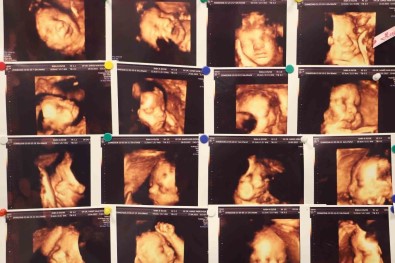

Tibbi literatürde abortus yani düsük olarak tanimlanan gebelik kaybi, bebegin 500 gram agirligina ulasmadan veya 20’inci haftadan önce çesitli sebeplerden ötürü gebeligin sonlanmasi anlamina geldigini açiklayan Dr. Evsen, genelde en sik ilk 3 aylik dönemde görülebilmekte oldugunu dile getirdi.

"Klinik olarak saptanan gebeliklerin yüzde 10-15’i düsükle sonuçlanmakla beraber bu durumun tekrar etmesi yani tekrarlayan gebelik kayiplarinda oran Yüzde 3 ila 5’tir. Tekrarlayan gebelik kayiplarinda en sik kromozomal sikintilar olmakla beraber, genetik anomaliler, hormonsal sikintilar, kan pihtilasmasi, rahmin yapisal bozukluklari, annede var olan diyabet ve guatr gibi sistemin hastaliklar, annede tekrarlayan enfeksiyonlar, bagisiklik sistemi sorunlari ve çevresel faktörler görülebilmektedir."